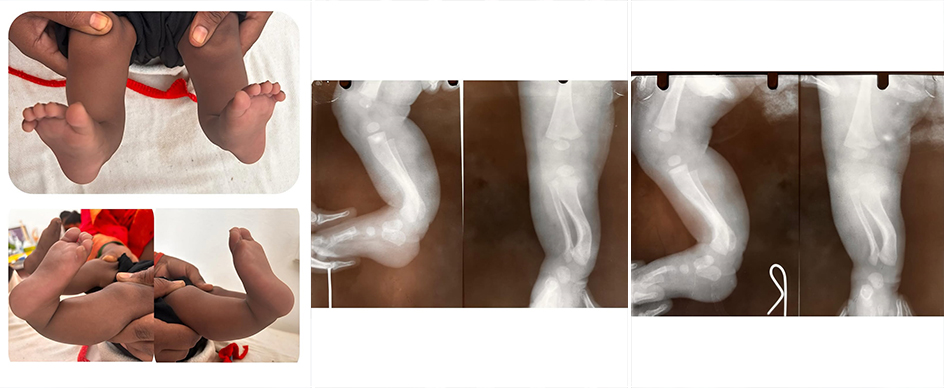

Congenital posteromedial bowing of the tibia and fibula is a rare birth condition where a baby is born with an inward and backward curvature of the lower leg bones. It may look unusual but is usually not painful and often improves with time.

βœ”οΈ Curved leg (visible bowing)

βœ”οΈ One leg appearing shorter